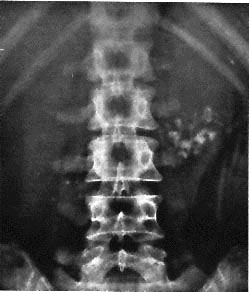

A 52-year-old woman comes to the physician as a new patient because of a 5-day history of temperatures to 38.2°C (100.8°F) and cough productive of thick, gray-green sputum. She says the sputum is difficult to cough up. During the past 15 years, she has had similar symptoms twice yearly, which resolved after treatment with antibiotics. Because of lack of insurance during this time, she was treated at urgent care clinics. She has no known allergies and no history of serious illness. Her only medication is an over-the-counter cough suppressant. She does not smoke cigarettes or use illicit drugs. She drinks three glasses of wine weekly. She is 170 cm (5 ft 7 in) tall and weighs 91 kg (200 lb); BMI is 31 kg/m2. Her temperature is 38°C (100.4°F), pulse is 80/min, and blood pressure is 138/84 mm Hg. Pulse oximetry on room air shows an oxygen saturation of 94%. On pulmonary examination, there is an increased expiratory phase; rhonchi and faint wheezes are heard bilaterally. A CT scan of the chest is shown. Which of the following is the most likely diagnosis?

An x-ray of the abdomen is shown. Which of the following is the most likely diagnosis?